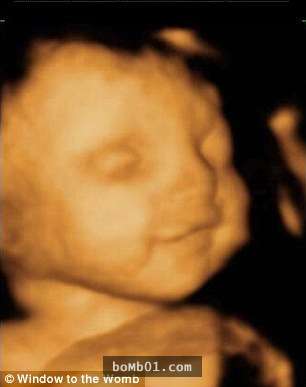

▼左邊這個寶寶看起來不開心,右邊這個寶寶卻笑得很歡樂。